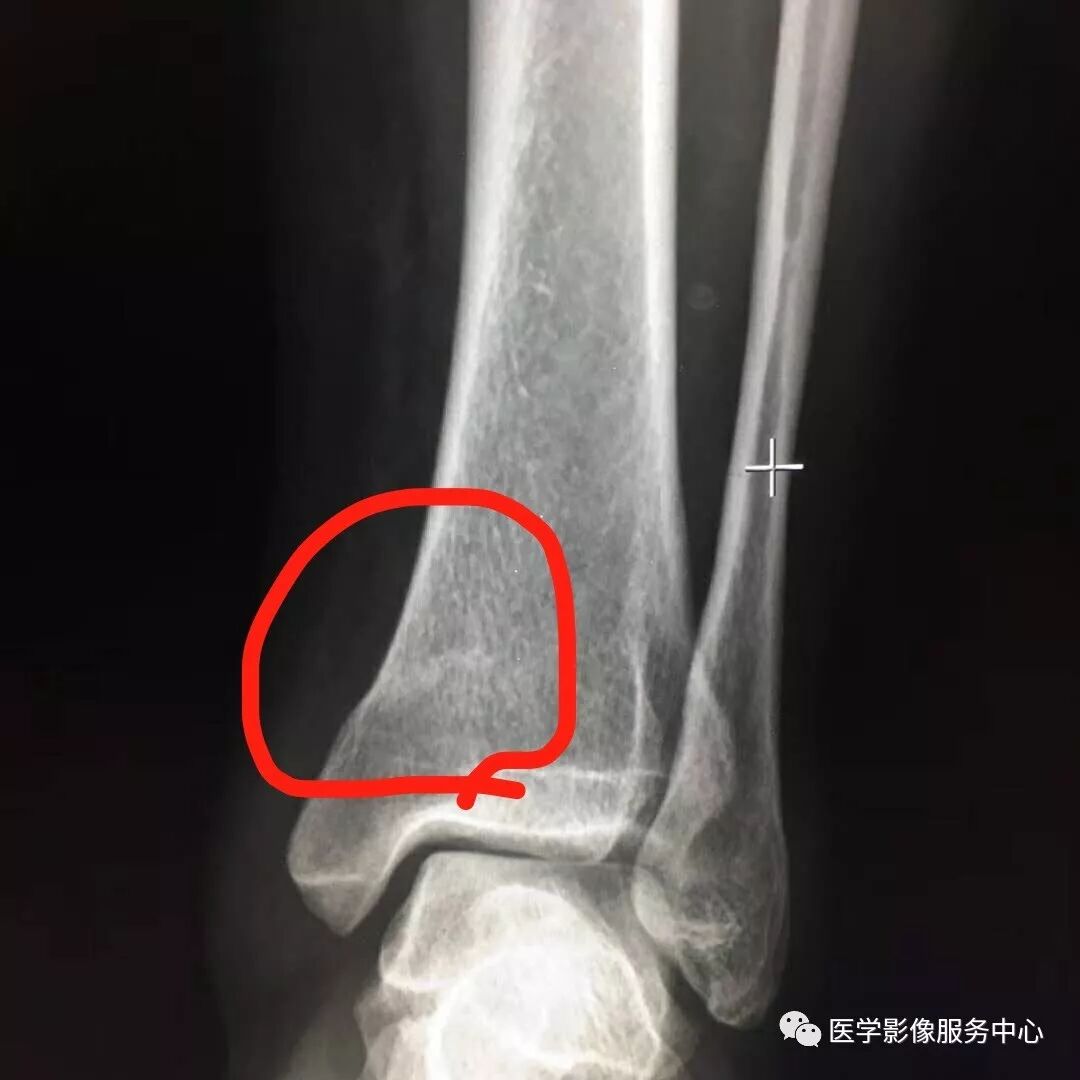

Pilon骨折常常伴随极度粉碎的骨折和严重的软组织损伤,选择合适的手术入路就成了手术的关键。